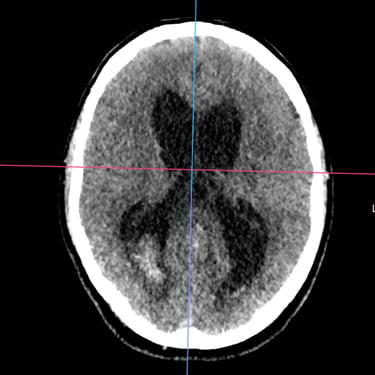

Hidrocefalia Posthemoventricular: Tratamiento con Derivación Ventriculoperitoneal

La hidrocefalia posthemoventricular se produce por alteración en la circulación y absorción del líquido cefalorraquídeo tras una hemorragia intraventricular, generando dilatación ventricular y deterioro neurológico progresivo. Cuando el manejo médico resulta insuficiente, la derivación ventriculoperitoneal constituye el tratamiento quirúrgico de elección. Este procedimiento permite drenar el exceso de líquido cefalorraquídeo desde los ventrículos cerebrales hacia la cavidad peritoneal, reduciendo la presión intracraneal y mejorando los síntomas neurológicos. La intervención oportuna contribuye a estabilizar la función cerebral y a optimizar el pronóstico funcional del paciente.